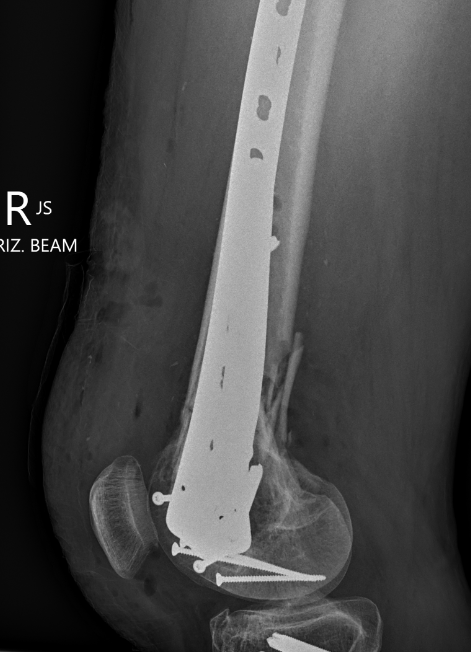

Type C: Complete articular

Xray / CT

Options

Dual Plate

Plate + Retrograde nail

Plate + Nail

Approach

1. Dual incision

- medial + lateral approach

- midlateral approach - split ITB, elevate vastus lateralis

- medial subvastus approach